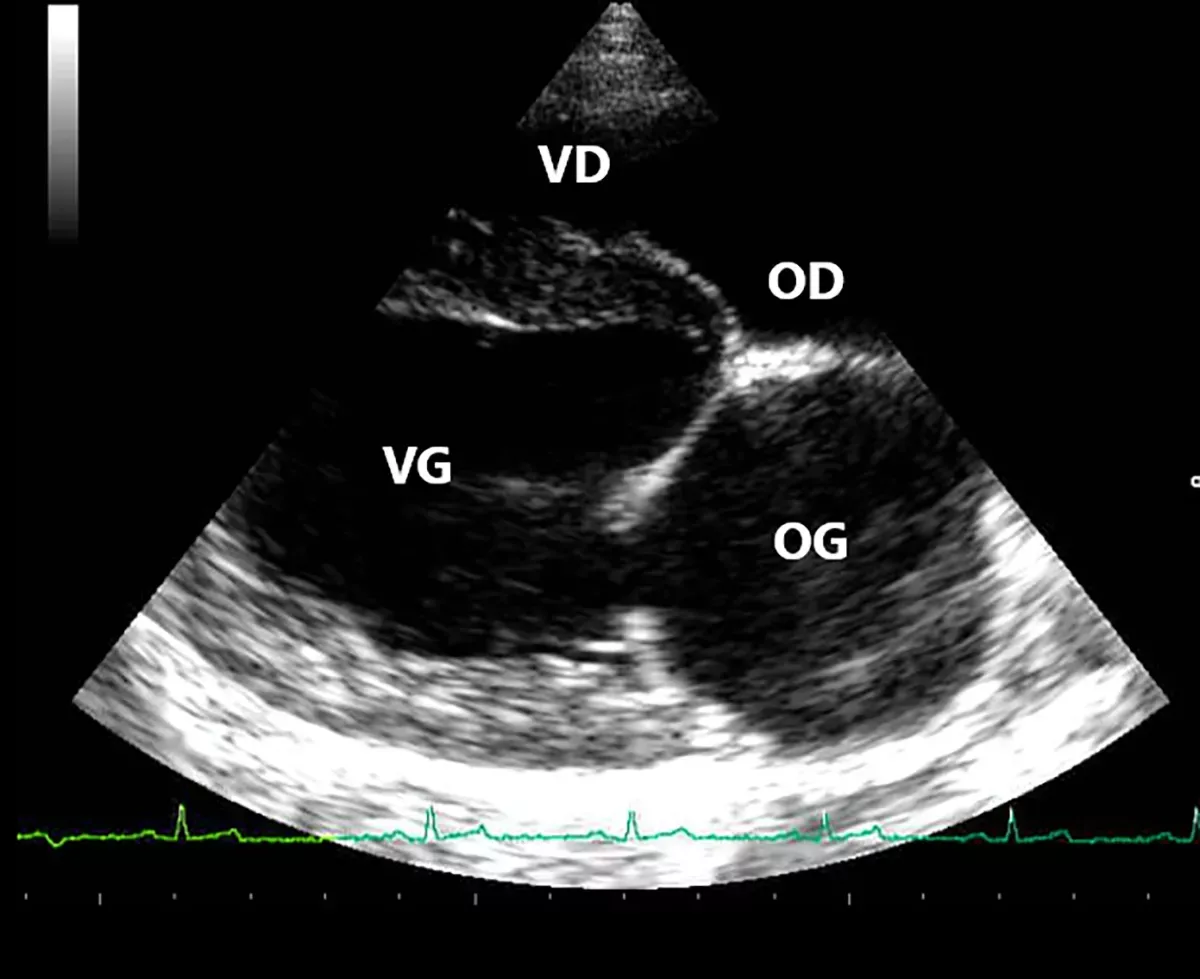

Dr. Rizza volgt momenteel een residency in medische beeldvorming, wat leidt tot certificering door het European College of Veterinary Diagnostic Imaging (ECVDI).